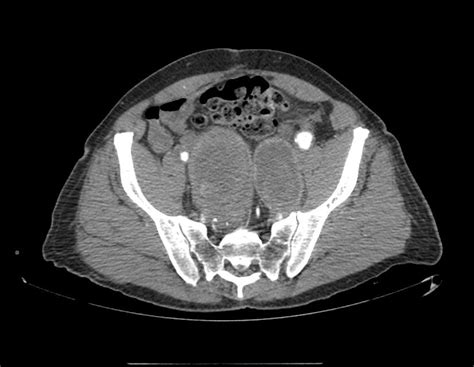

Diagnosis: How Doctors Find Internal Iliac Artery Aneurysms

So, you’ve got some symptoms, or maybe you’re in a high-risk group and your doctor suggests a check-up. How do doctors actually find these internal iliac artery aneurysms? Well, thankfully, there are several effective diagnostic tools available. The first step is usually a physical examination . Your doctor might be able to feel a pulsating mass in your abdomen or pelvic area, especially if the aneurysm is large. They will also take a detailed medical history, asking about your symptoms, family history of aneurysms, and risk factors like smoking and high blood pressure. If there’s a suspicion of an aneurysm, imaging tests are the next crucial step. Ultrasound is often the initial imaging modality used. It’s non-invasive, readily available, and can provide a good view of the iliac arteries, helping to identify the presence, size, and location of an aneurysm. However, ultrasound can sometimes be limited by factors like obesity or bowel gas. For more detailed and definitive imaging, doctors often turn to Computed Tomography (CT) scans or Magnetic Resonance Angiography (MRA) . A CT scan, especially a CT angiography (CTA), uses X-rays to create detailed cross-sectional images of your body. CTA involves injecting a contrast dye into your bloodstream, which highlights the blood vessels, allowing for very precise visualization of the aneurysm, its dimensions, and its relationship to surrounding structures. MRA uses magnetic fields and radio waves to create detailed images of blood vessels, and it’s another excellent option, particularly for patients who may need to avoid radiation or contrast dye. Sometimes, a traditional angiogram might be performed. This is a more invasive procedure where a thin, flexible tube (catheter) is inserted into an artery (usually in the groin) and guided to the iliac artery. Contrast dye is injected directly into the artery, and X-ray images are taken. While it’s more invasive, it can provide very detailed information about the blood vessels and is often used when planning for treatment. The choice of imaging test often depends on factors like the availability of the technology, the patient’s overall health, and the specific information the doctor needs. The goal of these diagnostic tests is not just to confirm the presence of an aneurysm but also to accurately measure its size, assess its shape, and determine its exact location. This information is critical for deciding on the best course of action, whether that’s watchful waiting or immediate intervention. So, rest assured, if an internal iliac artery aneurysm is suspected, doctors have a robust arsenal of tools to detect it accurately. Remember, early detection is key to successful management and preventing serious complications, so don’t hesitate to discuss any concerns with your healthcare provider, guys. It’s all about getting the right information to make informed decisions about your health.